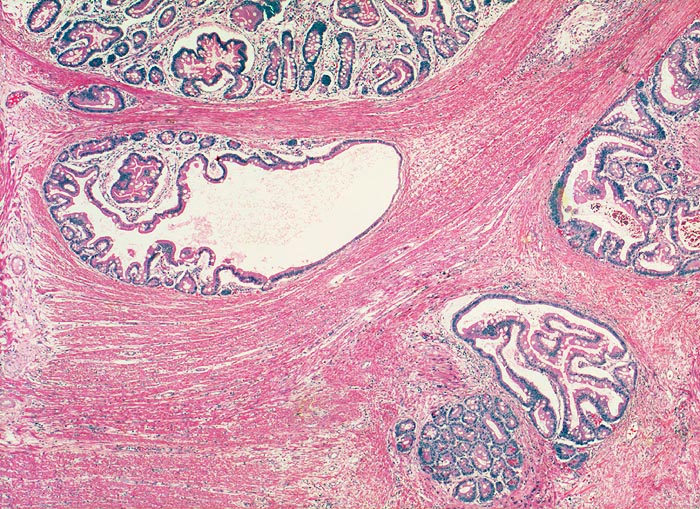

AP/ Peutz-Jeghers Polyp, Dünndarm

Peutz-Jeghers Polyp, Dünndarm

Jejunum

Pathologischer Befund